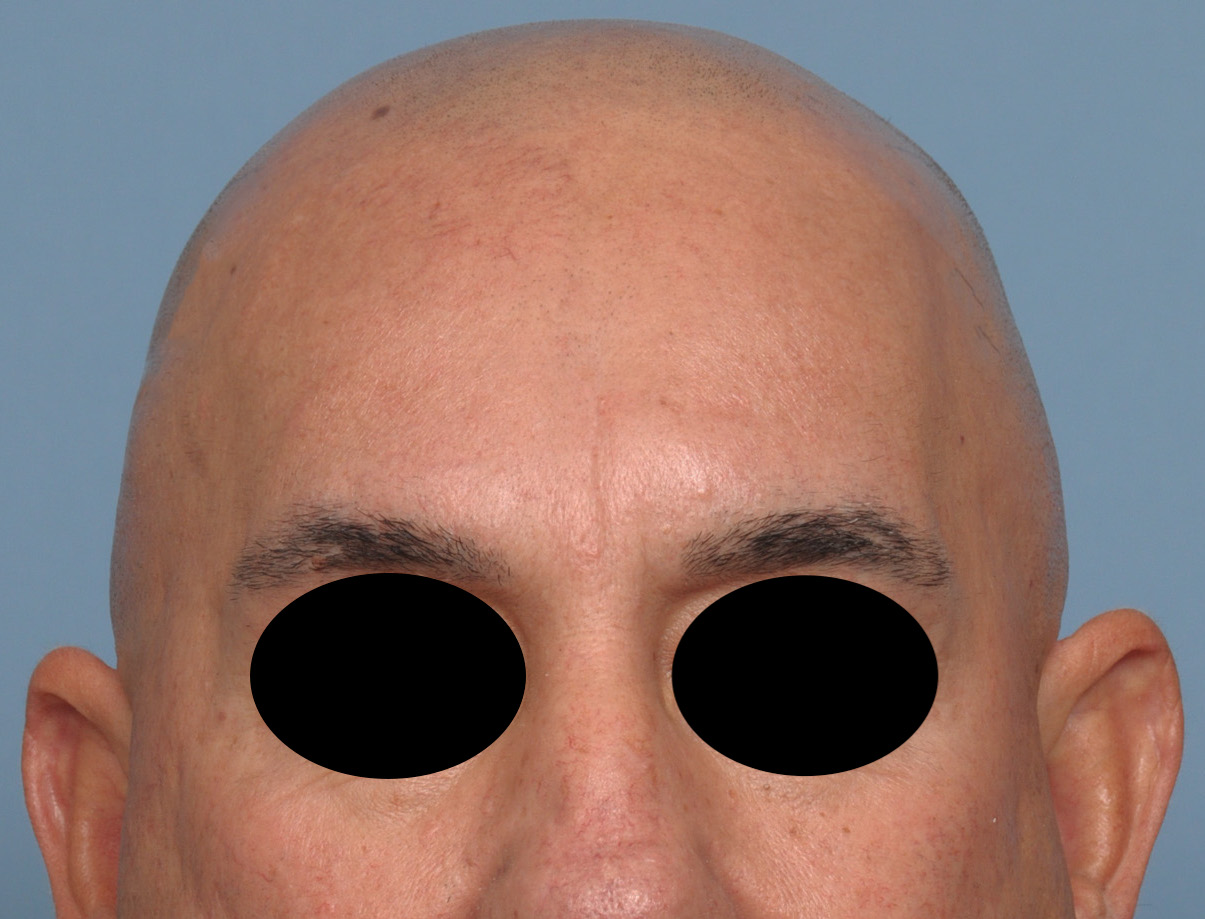

Patient 100

Desire for reshaping of an asymmetric flat back of the head in a shaved head male.

A combined back of the head reshaping procedure was done with a custom skull implant, sagittal ridge reduction and a right temporal muscle reduction.

Desire for reshaping of an asymmetric flat back of the head in a shaved head male.

A combined back of the head reshaping procedure was done with a custom skull implant, sagittal ridge reduction and a right temporal muscle reduction.